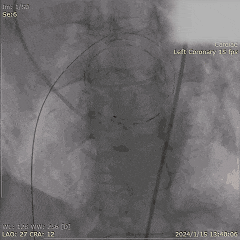

Step 3. 主动脉根部及冠状动脉造影

Step 4. 行PBMV术治疗